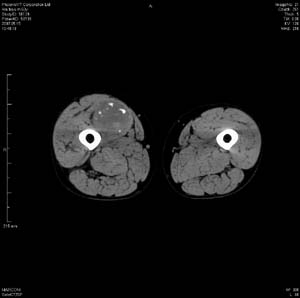

男 63岁 右大腿无痛性肿块11年,x片右大腿软组织肿块影,余无明显异常.ct值-13__239hu

右大腿股内侧股与收肌间隙间多发囊实性占位,界清.内示斑点状钙化.局部骨质无异常.肌肉推压移位表现.

考虑肌间隙病变.可有1,神经来源肿瘤.2,血管来源病变.3,淋巴来源肿瘤.4,脂肪来源肿瘤.5,滑膜来源肿瘤.结合病史只能考虑良性占位.建议增强或mri进一步分析.

同意,病史较长,病变周围分界清晰,考虑良性病变。病灶内有多发斑点状钙化,沿肌间隙生长,血管瘤或淋巴管瘤首先考虑。